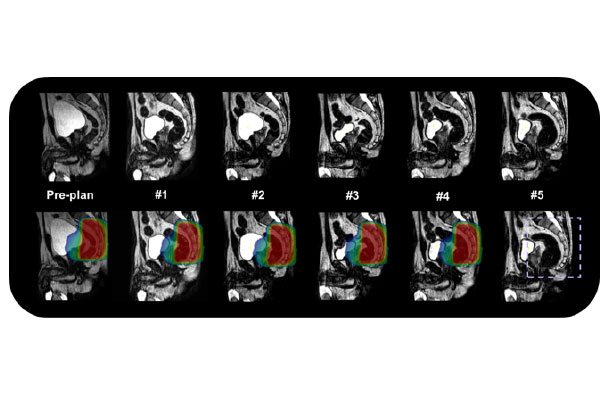

原先复杂的肝脏和胰腺肿瘤由于图像引导可视性差都不太适合进行放疗。由于高精度磁共振图像引导可无创的分辨肿瘤和危及器官,使用实时自适应放疗技术,确保剂量学准确投射,对肝、肾、肠道等器官有比较好的保护。

随着生活水平的提高,前列腺癌大发病逐渐上升,剂量学研究和初步的临床实践已经显示调强是当今放疗前列腺癌的最好照射技术,有广泛的应用前景,磁共振引导技术可以更好的对前列腺组织进行分辨,可以进行功能保留行治疗及肿瘤消融治疗,同时磁共振功能成像技术也为治疗疗效提供生物学依据。